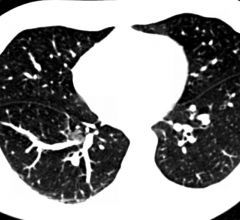

Data regarding screening of individuals at high risk for lung cancer with low-dose computed tomography (CT) presented at the 2014 Annual Meeting of the American Society of Clinical Oncology (ASCO) overestimates the costs and number of false positive exams due to its reliance on an outdated 4 mm size threshold for defining a positive screen.

July 30, 2014 — A study by Gareen et al, published July 25 in Cancer, the incidence and effects of anxiety associated with false positive or other results of computed tomography (CT) lung cancer screening exams are far less than claimed by some in the medical community.

The American College of Radiology (ACR) is accepting applications for its new ACR Lung Cancer Screening Center program, which recognizes facilities committed to providing quality screening care to patients at the highest risk for lung cancer.

The American College of Radiology said it is deeply disappointed at the failure of the Medicare Evidence Development & Coverage Advisory Committee (MEDCAC) to vote in support of national Medicare coverage of low-dose computed tomography (LDCT) screening for patients at high risk for lung cancer.